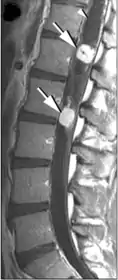

Вузол гемангіобластоми складається з клубка тонкостінних судин. При введенні в кров контрастних речовин пухлина накопичує введені препарати, завдяки чому добре контрастується на ангіограмах, комп'ютерних та магнітно-резонансних томограмах. Визначаються великі патологічні артерії і вени, можуть виявлятися артеріо-венозні шунти. При проведенні комп'ютерної (КТ) та магнітно-резонансної (МРТ) томографії діагностуються дві форми пухлини — вузол з або без кістозного компонента. Перша форма характеризується тим, що великі кісти виконують велику частину об'ємного утворення. Вузол може взагалі не визначатися з допомогою нейровізуалізаційних методів дослідження.

Кіста гемангіобластом зазвичай округлої або овальної форми, на комп'ютерній томографії має низьку щільність (8-14 одиниць Хаунсфілда). При введенні контрастних речовин щільність її вмісту і стінок не змінюється. Вузол пухлини визначається на КТ у вигляді вогнища підвищеної щільності, частіше негомогенной зернистої структури. Розташовується на одній зі стінок кісти, вдаючись у її просвіт, добре накопичує контрастну речовину.

При кістозній формі пухлини на магнітно-резонансних томограмах добре визначається кістозний компонент, який характеризується низькою інтенсивністю сигналу на Т1 - і високим сигналом на Т2-зважених томограмах. На цьому тлі добре візуалізується пристеночно розташований солідний вузол гемангіобластоми, котрий добре накопичує контрастну речовину.

При солідній формі гемангіобластоми в стромі новоутворення відзначається наявність округлих і звивистих ділянок втрати сигналу за рахунок кровотоку у великих судинах пухлини.

Гемангіобластоми в області хребетного каналу

Гемангіобластоми в області хребетного каналу зазвичай розташовуються інтрамедуллярно (в спинному мозку), але можуть міститися і экстрамедуллярно (поза спинним мозком). У 50 % вони вражають грудний відділ і в 40 % шийний. Так як гемангіобластоми являють собою багатоваскуляризированні новоутворення, то їх клінічна маніфестація може дебютувати субарахноїдальним крововиливом[25].

У більшості випадків гемангіобластоми в області хребетного каналу являють собою солітарне утворення, проте в 20 % можуть спостерігатися множинні новоутворення (як правило, при хворобі Гіппеля — Ліндау). Приблизно в половині випадків (43-60 %) утворюються сирінгоміелічні порожнини. Кісти можуть досягати великих розмірів, розташовуючись вище і нижче солідного вузла пухлини[26][27].